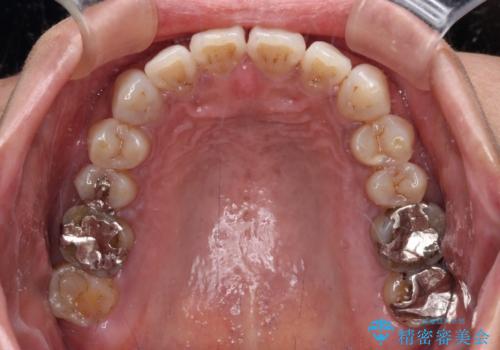

極端な上下前歯の開咬を改善 オープンバイトのインビザライン矯正

治療前に、いくらインビザライン矯正がオープンバイトを得意としているとは言え、さすがに限界があるだろうと思っておりましたが、前歯でレタスが噛めるまで改善することができました。

顔の印象も大きく変わり、患者様には大変満足していただきました。